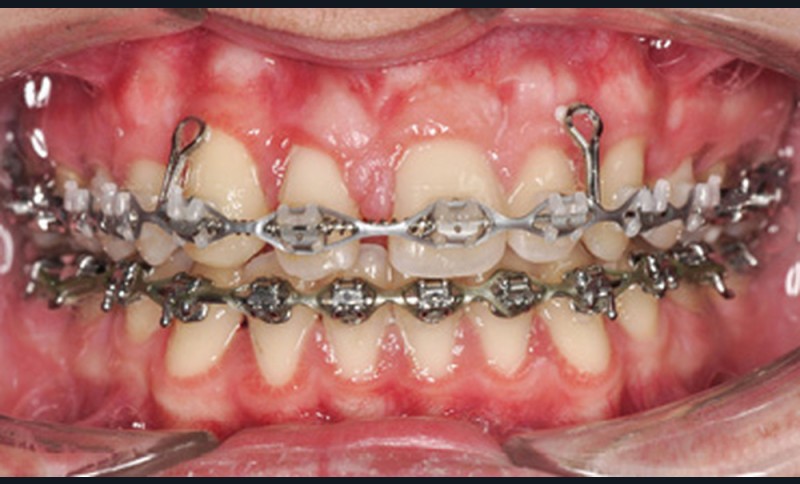

Le nivellement a nécessité trois arcs en Copper-NiTi (.014/.016 x .022/.019 x .025). Les mécaniques intra arcades (fermeture des espaces) et interarcades (élastiques de tractions intermaxillaires de classe II) ont été effectuées sur des arcs en acier .019 x .025. La gestion asymétrique de la mécanique de rétraction maxillaire a débuté par le recul de 23 (ancrage postérieur dentaire + élastiques intermaxillaires de classe II). Une fois 23 symétrisée avec 14 (substituant la 13), le centrage de 12 a débuté pour le remplacement de la 11. La rétraction du groupe antérieur par un arc à boucles de rétraction en acier .019 x .025 permet d’ajuster le torque radiculo-palatin pour contrer le rabbiting antérieur (fig. 2a-c).

Lors de la phase de finitions, une séance de réévaluation radiographique des axes radiculaires (fig. 3a-b) a permis de corriger les défauts de collage et d’étudier les mouvements squelettiques et dento-squelettiques obtenus.